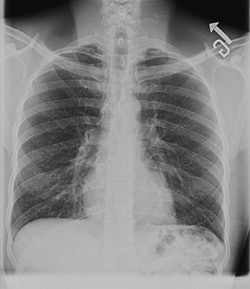

![]() |

| A digital chest image taken with GE's VolumeRad technology. |

VolumeRad collects 40 to 60 low-dose tomographic slices in a five-second sweep of the system's overhead tube crane. The slices can then be reconstructed into volume images. GE believes the technique can be useful for applications such as ruling out pathology in patients who otherwise might be sent on for more expensive modalities like CT and MRI.

The company has been shipping VolumeRad for the past three months, and has 100 of the systems installed.